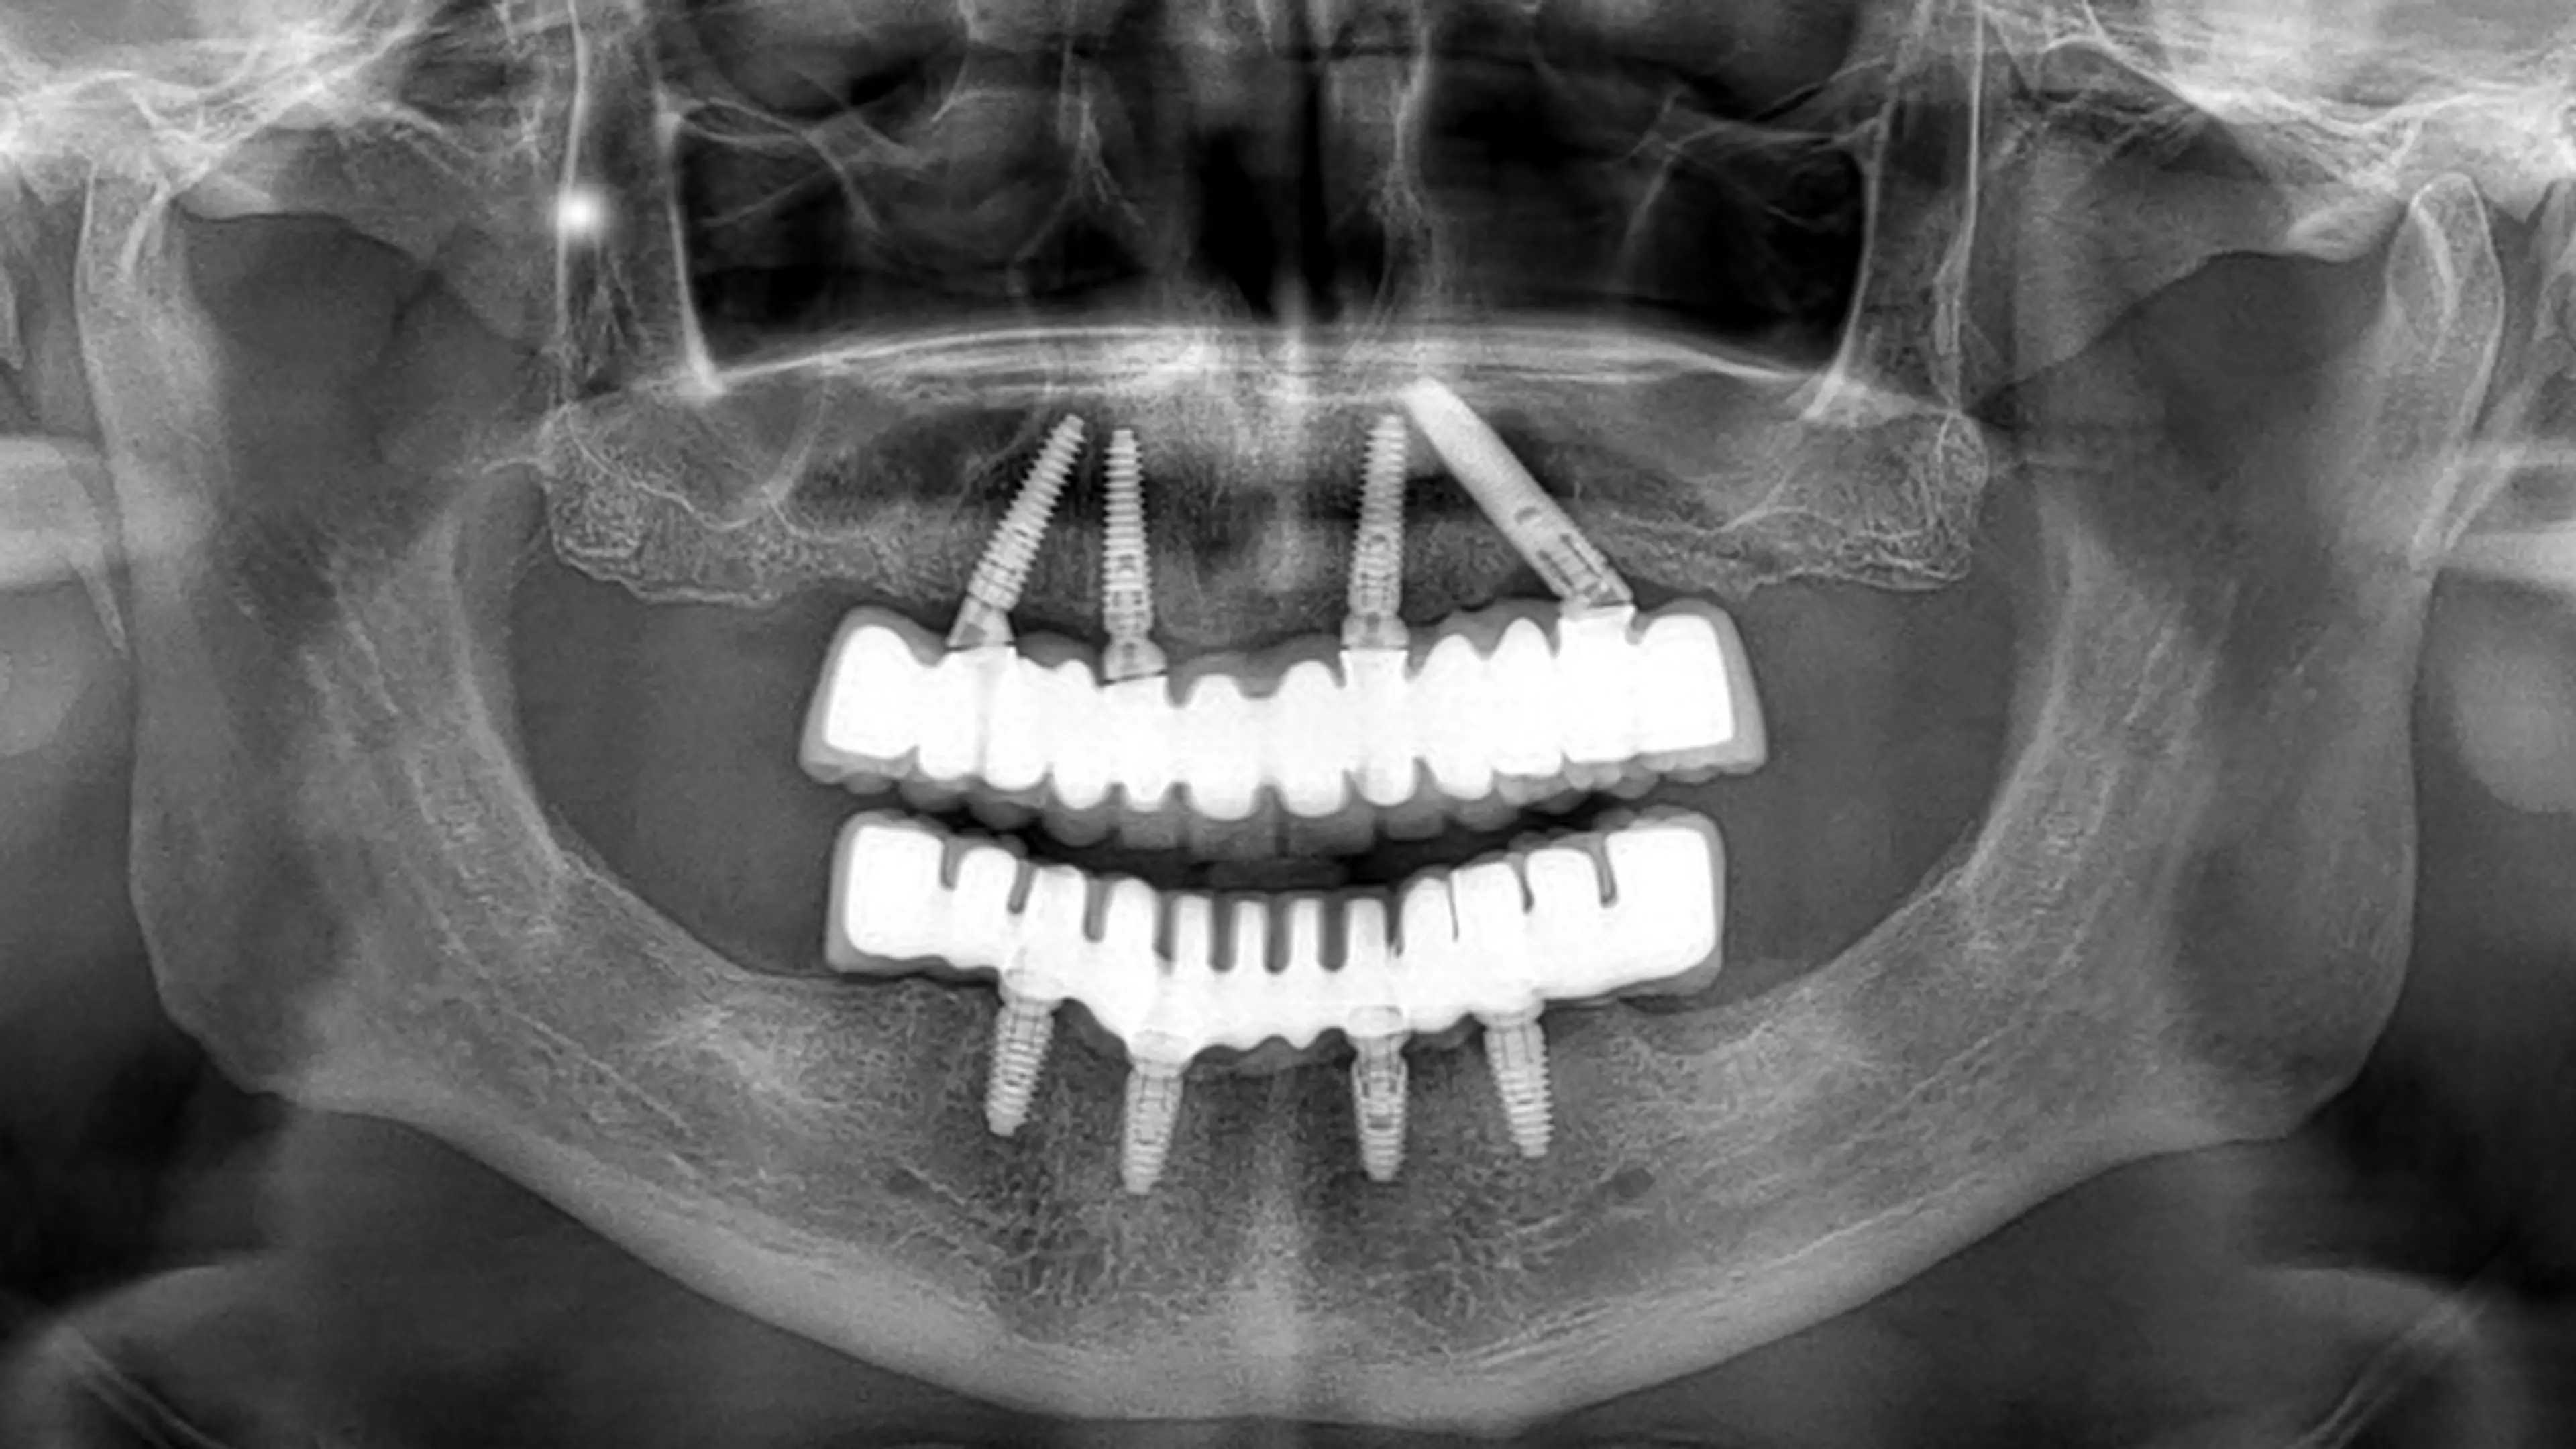

本质上,计算机化种植体分析结合了三维成像(3D imaging)锥形束计算机断层扫描(CBCT)CAD/CAM系统等多种技术,帮助我们精准定位种植体的最佳植入位置。这些工具可以采集患者颌骨、牙龈及周围结构的详细实时数据,生成口腔的虚拟模型。这样,牙科团队可以在实际操作前,对整个种植过程进行细致的规划。

首先,需要获取您口腔的详细影像资料。在 Ye-on 牙科诊所,我们采用锥形束CT扫描,这是一种能够提供牙齿、牙龈和骨骼高精度三维图像的先进技术。与传统的二维X光片相比,这种成像方式可以让我们从360度全方位清晰观察您的口腔结构,获取更为细致的信息,从而为精准的治疗方案制定提供有力支持。

在获得影像资料后,我们会将数据导入专业软件,通过虚拟环境模拟种植手术。三维模型可以帮助我们直观地看到种植体的具体位置,同时考虑骨密度、邻牙排列以及可能存在的解剖结构问题(如神经或上颌窦的位置)。借助软件,我们能够科学地确定种植体的大小、角度和深度,确保手术方案的安全与合理。

计算机种植体分析的一大优势,就是可以实现引导式手术。通过计算机软件,我们能够制作出专属的手术导板——这是一种贴合您牙齿和牙龈的定制模板,能够帮助医生以毫米级的精度植入种植体。手术导板能有效减少人为误差,让整个过程更加可控和安全。